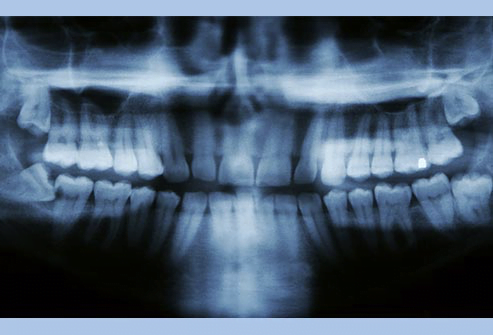

دندانهای نهفته

دندان نهفته، دندان دائمی میباشد که موفق به رویش نشده است. معمولا هنگامی اتفاق میافتد که دندان زیر یک دندان دیگر، استخوان و یا بافت نرم گیر کند. اگر این موضوع شما را اذیت نکند، دندانپزشک ممکن است توصیه کند که کاری با آن نداشته باشید. اما اگر این دندان مشکلساز شد و یا موجب آسیب به بافتهای اطراف شود، جراح دندان را خارج میکند.

مشکلات دندان عقل

اگر دندانپزشکتان میگوید دندانهای عقل شما بدون مشکل است، خود را خوش شانس بدانید. بیشتر افراد -۹۰ % – حداقل یک دندان عقل دارند که نهفته بوده یا قادر به رشد کامل نیست. دندان عقل میتواند موجب ایجاد پوسیدگی، آسیب به دندانهای مجاور و بیماری لثه شود. دندانهای عقل عموما بین سنین ۱۷ تا ۲۵ سالگی رویش مییابند. دندانپزشک شما باید روند رشد آنها را پیگیری کند. اگر مشکلساز شوند، ممکن است لازم باشد آنها را خارج کنید.